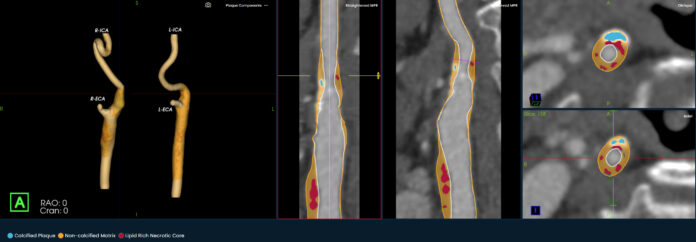

BOSTON — Elucid, an AI-driven medical technology company dedicated to providing physicians with more precise insights into atherosclerosis for patient-specific treatment decisions, announced the launch of PlaqueIQ, a new image analysis software for quantifying and classifying plaque morphology in the carotid arteries. PlaqueIQ is the first and only CT-based plaque analysis software indicated for the carotid vasculature and is designed to help physicians identify plaques at risk of rupture and develop personalized treatment strategies to prevent ischemic stroke.

PlaqueIQ introduces a breakthrough in stroke risk assessment by enabling non-invasive, histology-based analysis of plaque composition. The platform provides physicians with CT Virtual Histology, offering detailed quantification and classification of plaque morphology and the ability to identify lipid-rich necrotic core—the plaque type most strongly associated with cardiovascular and cerebrovascular events.

PlaqueIQ is the first FDA-cleared, non-invasive plaque analysis tool based on objective histology. It allows physicians to move beyond traditional population-based risk models and instead prioritize and personalize treatment based on individual plaque characteristics in both the coronary and carotid arteries. The technology assists clinicians in evaluating symptoms, assessing risk for future events such as heart attack or stroke, and creating personalized care pathways that reflect the biology of each patient’s disease.

When used together for coronary and carotid imaging, PlaqueIQ provides a unified, quantitative, and qualitative view of systemic atherosclerotic risk, enabling comprehensive vascular assessment through a single non-invasive scan.